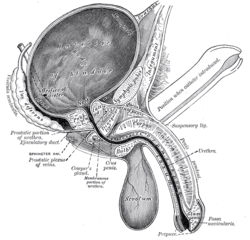

Vertical section of bladder, penis, and urethra.

Vertical section of bladder, penis, and urethra. The bladder can be seen highlighted in yellow in the illustration.

The bladder can be seen highlighted in yellow in the illustration.